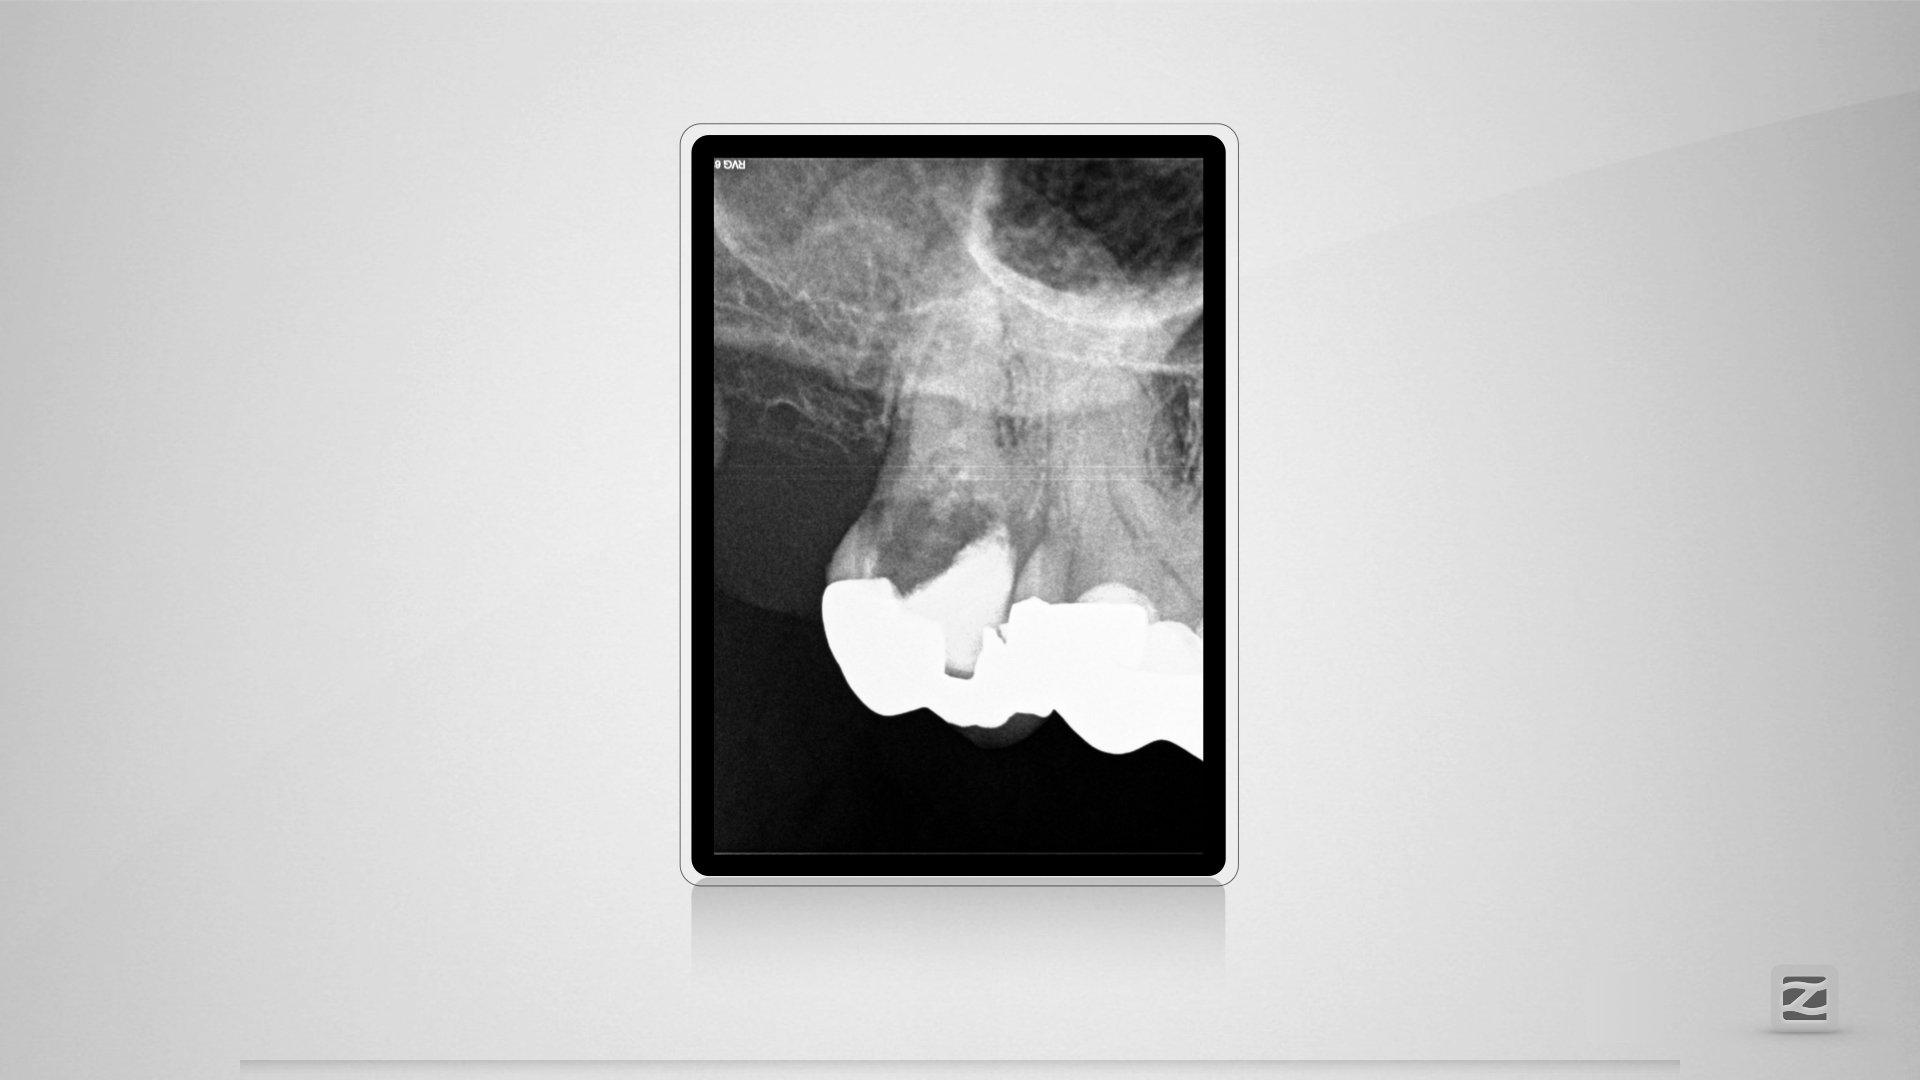

PerforationD.013

Übermut tut selten gut.